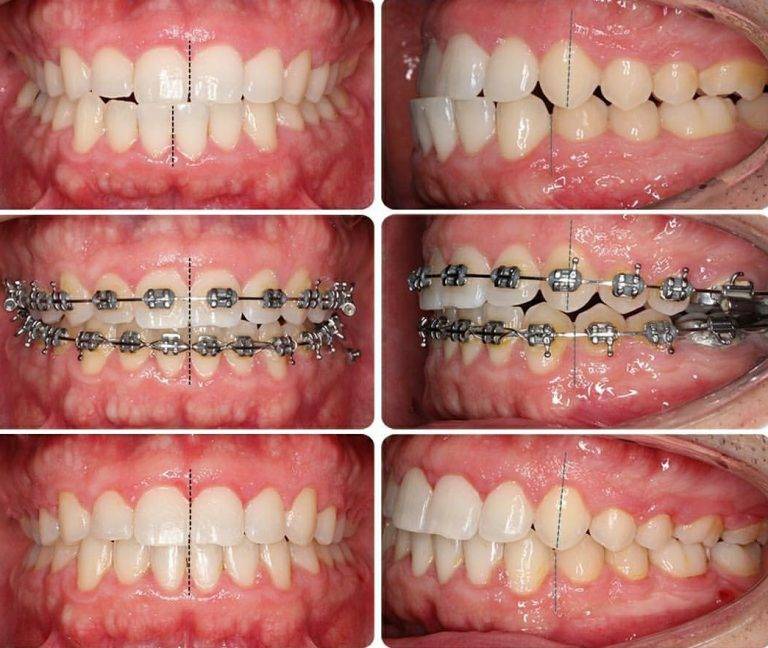

Результат до и после ношения брекетов